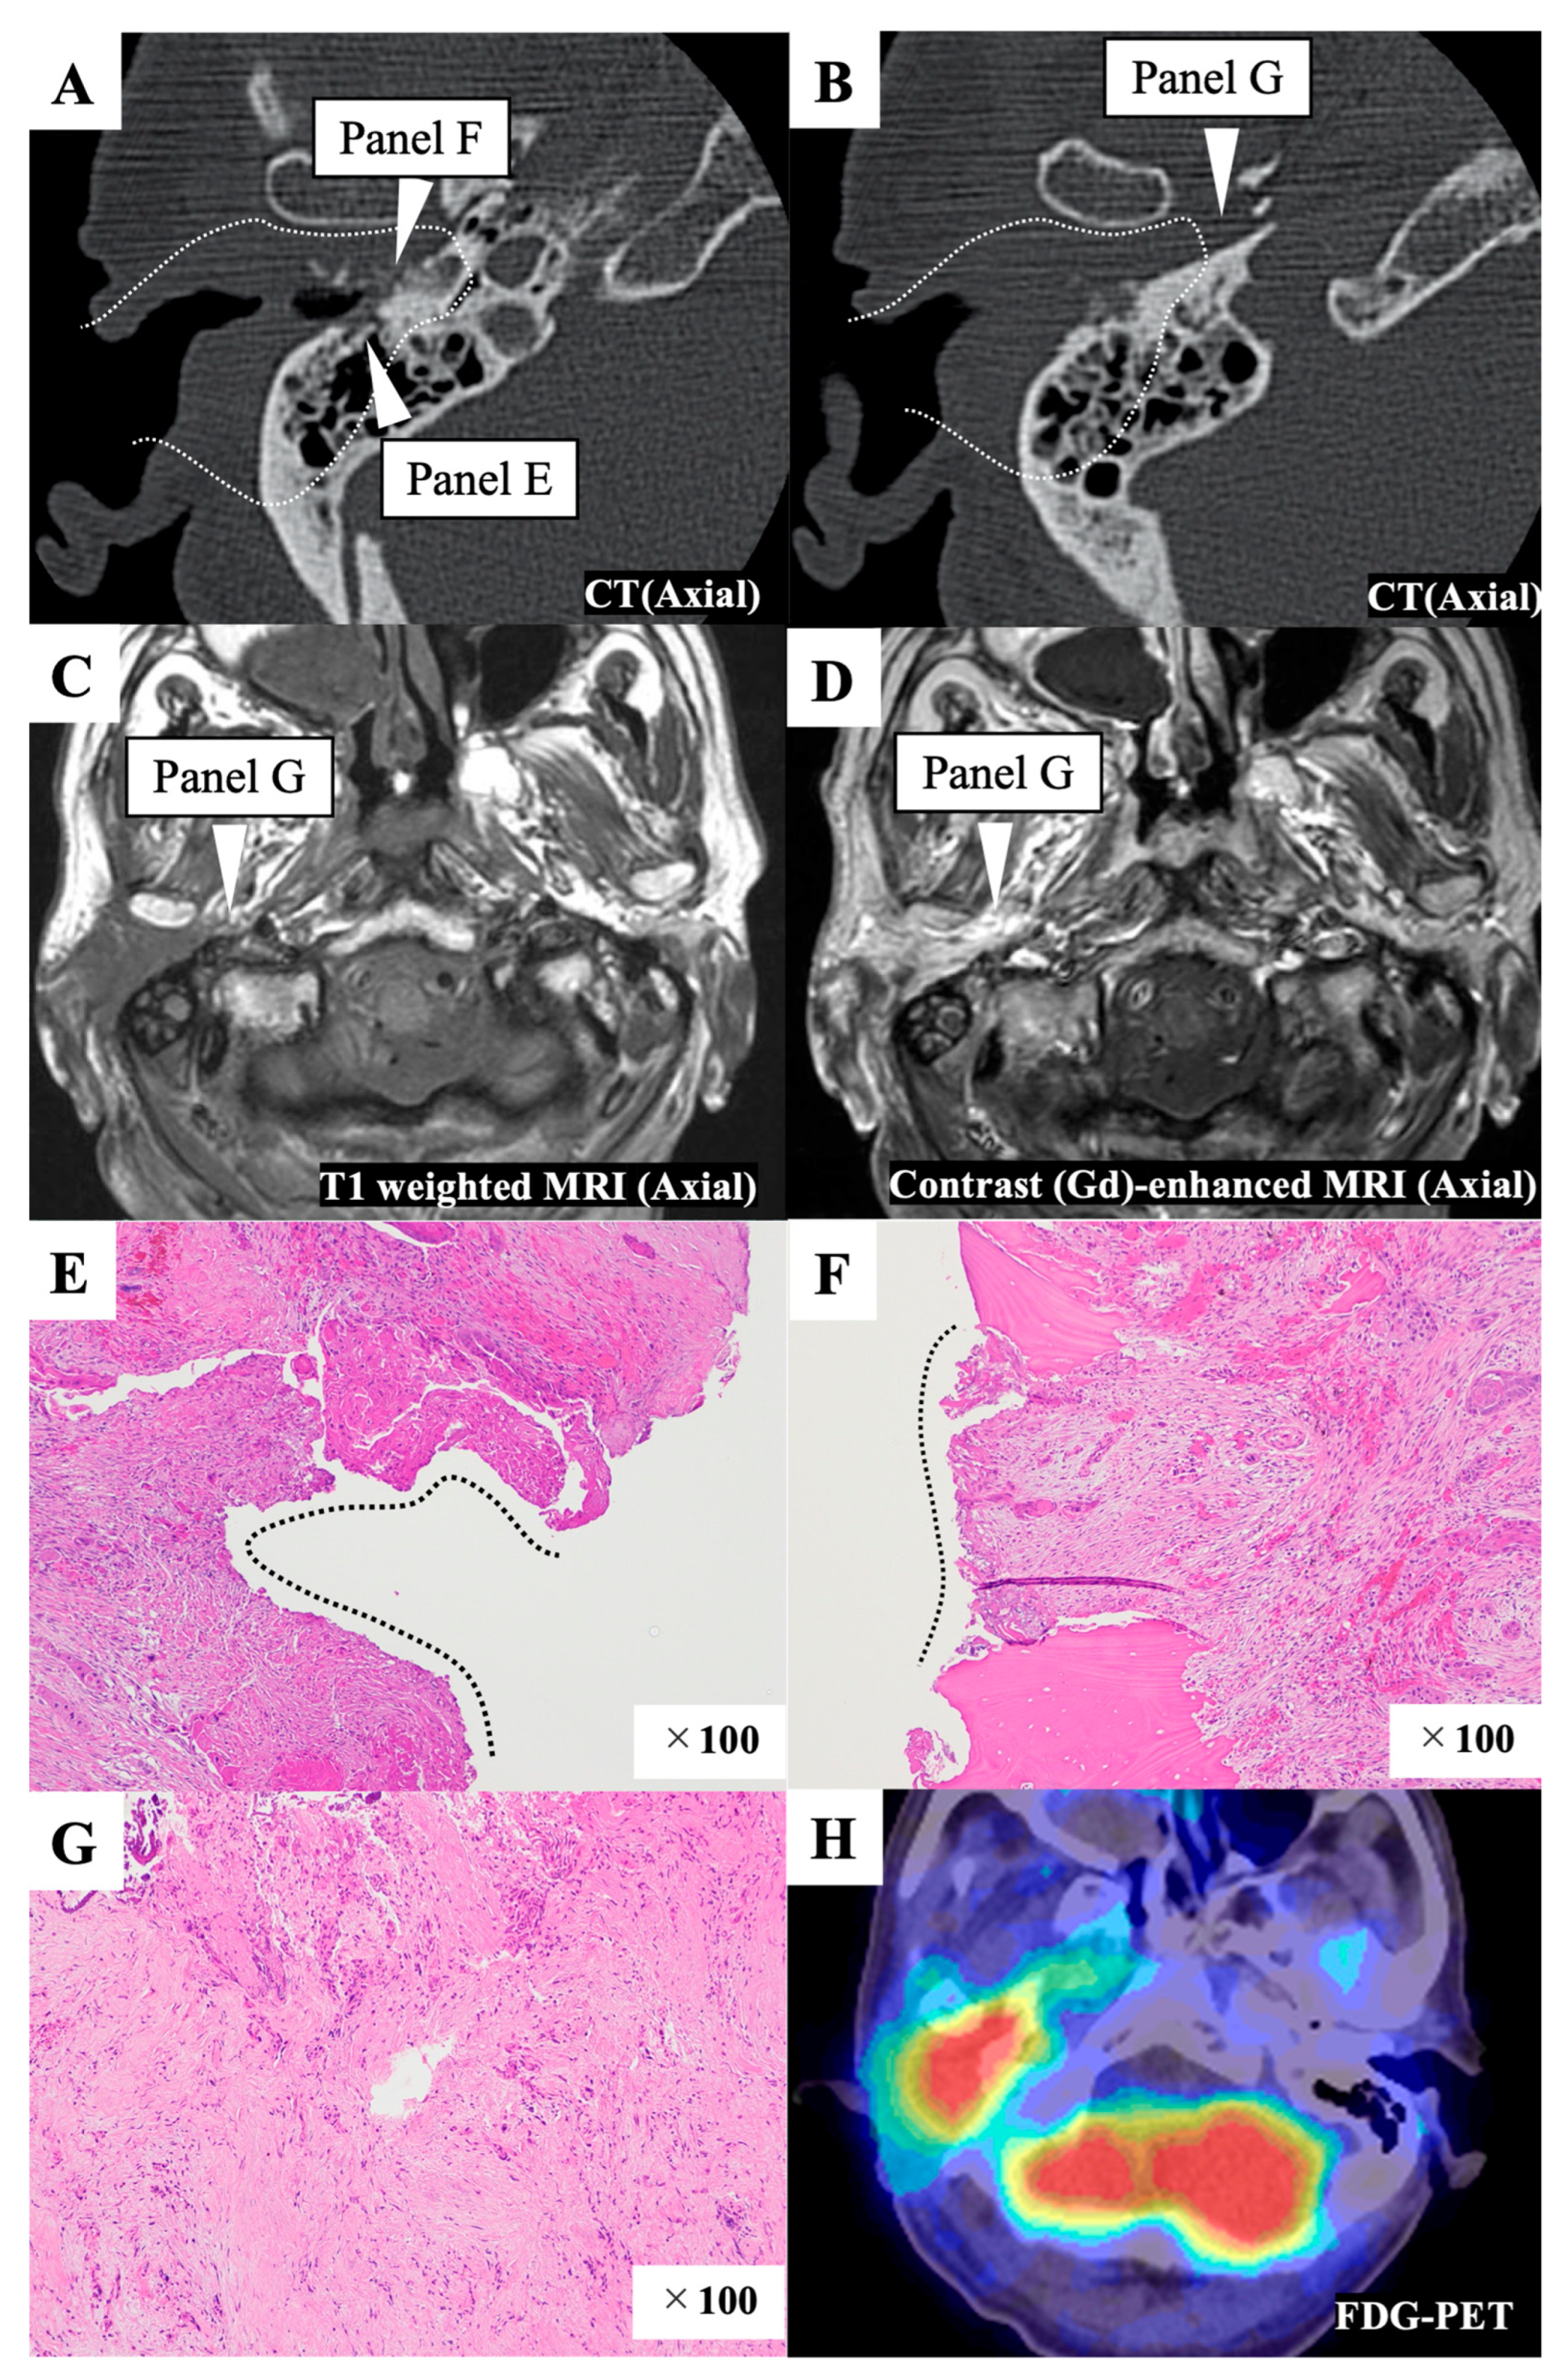

3.2.3. Case 32

| 32 | IC + CRT→Surgery | mSTBR | 4 | 0 | y4 | 0 | 2, 0, 2 | + | + | + | + | + | + | N,M | |||||||||||||